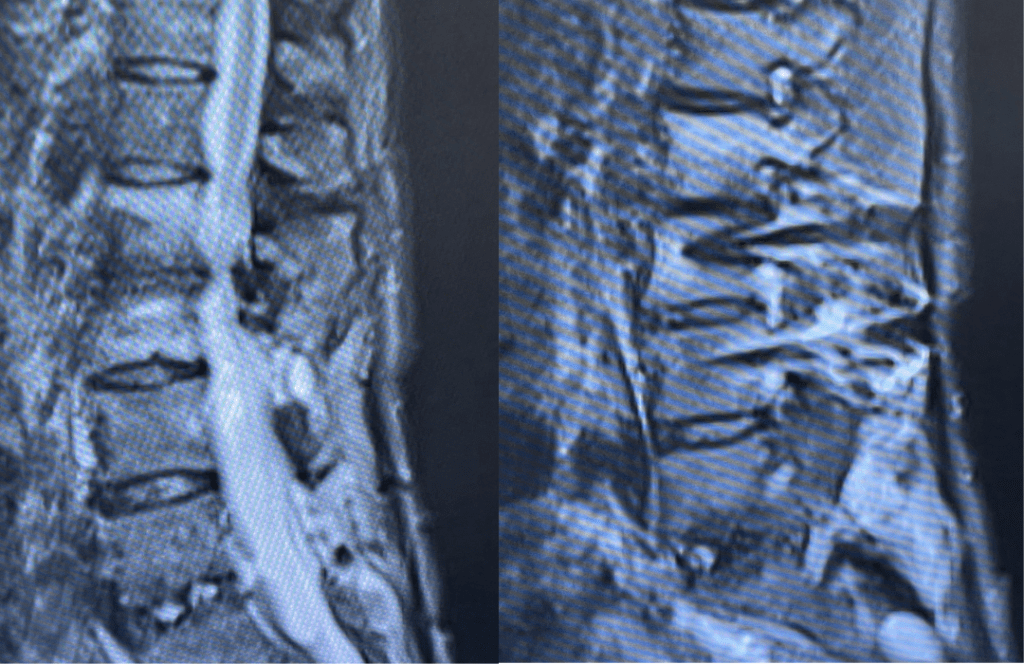

This 62-year-old female presents with chronic intractable low back pain with radiation down the front of her thighs. The patient had had two prior fusion surgeries: She initially had an L4-S1 fusion twelve years prior and a subsequent revision extension of her fusion at L3-4 that she had three years prior. She had a long-term history of smoking. She had mild hip flexor weakness, right greater than left. Imaging studies revealed next segment degeneration and stenosis at L2-3 (Figs. 1a and 1b and 2).

Figures 1a and 1b. Sagittal T2 MRIs of the lumbar spine demonstrating L2-3 stenosis after L3-4 instrumented fusion.